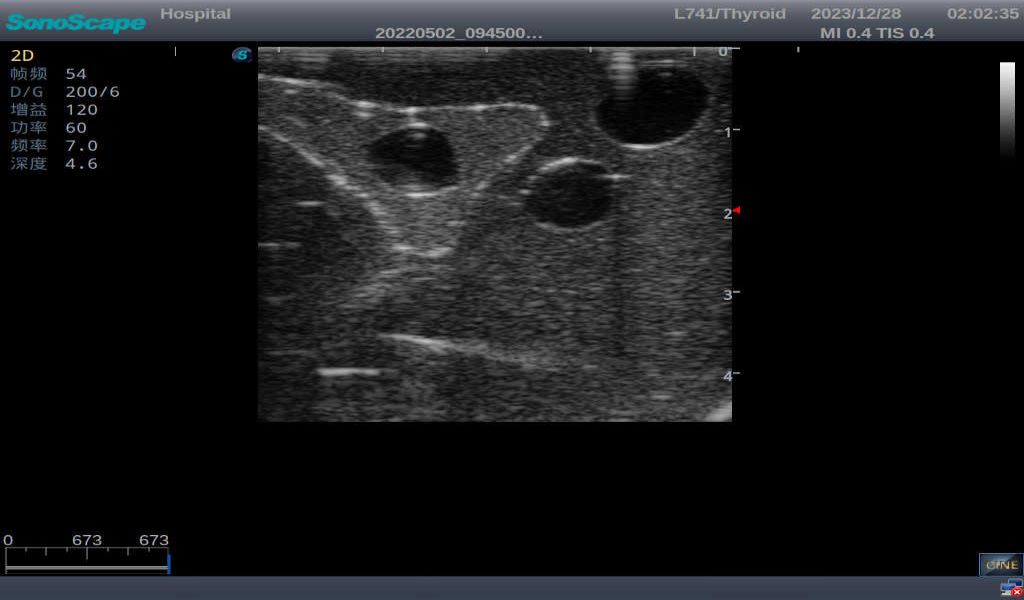

Nodular goiter with irregular border and varying sizes of low echo, isoechoic, or high echo nodules